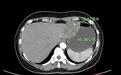

黄女士今年45岁,近半个月来上腹部持续出现饱胀感,尤其在饭后症状更为明显,她感觉不对劲,便来到武汉市普仁医院就诊。经过检查,医生发现,黄女士的肝脏上竟然藏着一个7.3厘米×4.5厘米的血管瘤,如同“苹果”般大小,黄女士随即被收入肝胆胰疝外科继续治疗。

患者肝脏上的血管瘤

“黄女士此前已有血管瘤病史,但并未引起足够重视。此次入院后,腹部增强CT检查明确提示为肝多发血管瘤,且血管瘤体积较大,已经对周围器官尤其是胃壁造成了压迫,导致上腹部不适。”肝胆胰疝外科主治医师罗刚指出,肝血管瘤虽然通常为良性肿瘤,但一旦血管瘤破裂,将可能引发大出血,后果不堪设想。